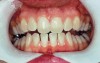

Depending on the level of staining, teeth with yellow, light brown, and orange stains as a result of aging, genetics, food, and drinks (and not developmental or systemic causes) usually respond within 1 to 4 weeks, while those with brown, orange, and white stains from fluorosis or stains caused by nicotine are slower to respond to bleaching—generally requiring 1 to 3 months of treatment.8 Even more resistant to whitening are teeth that tetracycline stained, which may appear dark gray, brown, or blue (Figure 1 and Figure 2). According to Haywood, whitening these teeth at home may take 6 months using 10% carbamide peroxide.8

Fig 1. Teeth with tetracycline stains before whitening treatment. (Photograph courtesy of Marcos Vargas, DDS, MS. Originally published in: da Costa JB. The Tooth-Whitening Process: An Update. Compendium. 2012;33(10). © AEGIS Publications, LLC. Used with permission.)